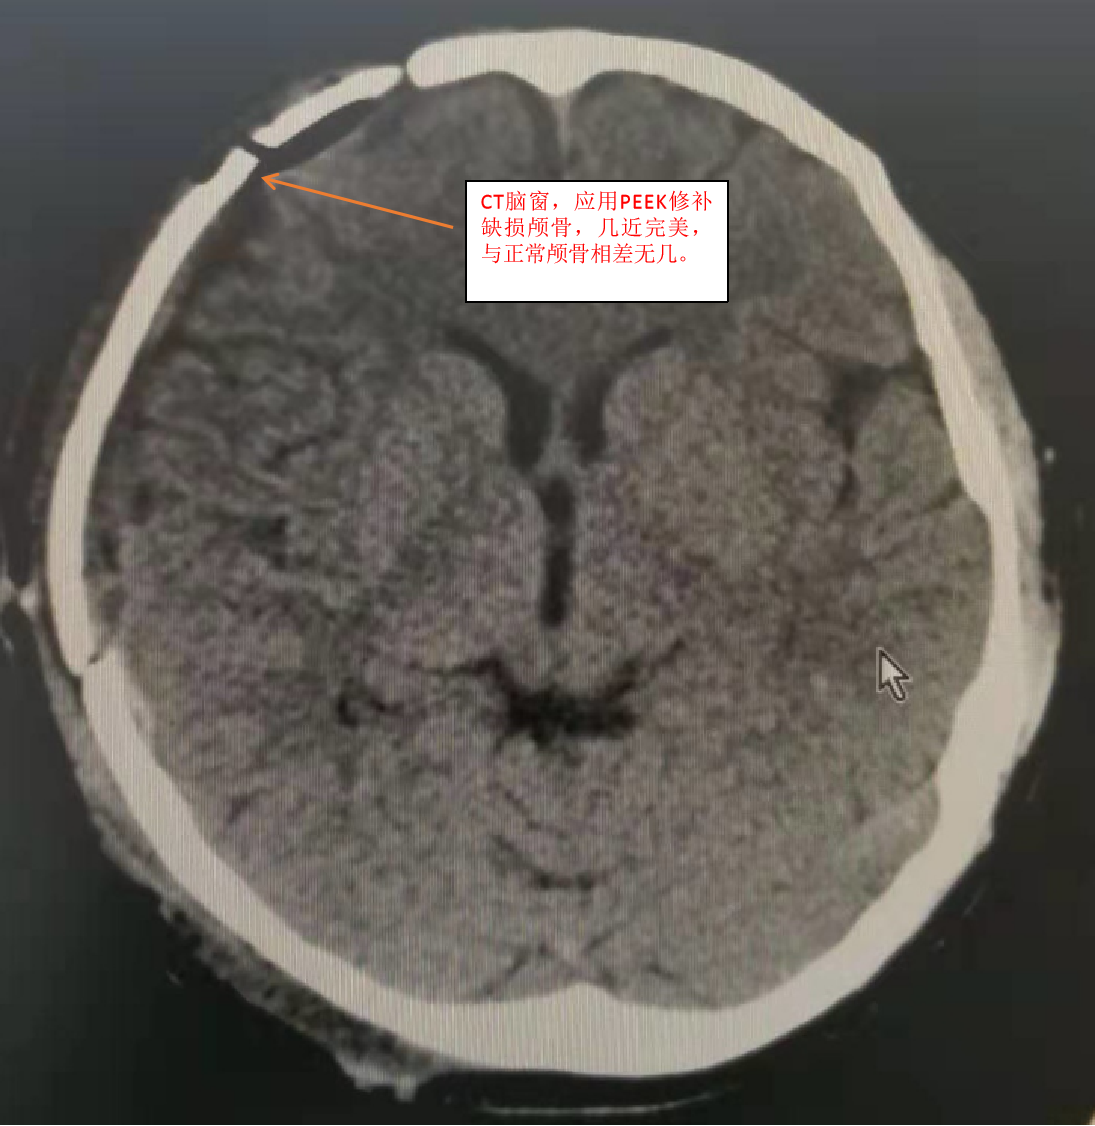

PEEK是一种什么材料?为什么它应用于颅骨修补术后会让一个国家的人民喜大普奔呢?重型颅脑损伤往往会去骨瓣减压,去骨瓣后往往会留有颅骨缺损,后期一般会行颅骨修补术,而修补材料的选择是一个大问题,从一开始的应用骨水泥、自体骨,到肽网等材料,这些材料各有优缺点,而且许多材料缺点非常明显。而PEEK(学名聚醚醚酮)是一种新型的工程塑料,应用于颅骨修补术是一个历史的飞跃。PEEK到底有什么优点呢?1、跟颅骨一样的厚度,硬度高,抗撞击不易变形,不导热,三维成形后镶嵌于颅骨缺损处,而不是向肽网那样覆盖予颅骨缺损处,再用连接板固定于颅骨,手术后的效果近乎完美。2、适用于各年龄阶段,尤其适合12岁以下的儿童,而目前最常用的肽网因儿童颅骨的继续发育不能使用。3、PEEK修补术后可以行核磁共振检查,而目前普通的钛网材料不能行核磁共振检查。

目前兰陵县人民医院颅脑创伤外科已经完成了12例此种手术,全部成功,无一例感染。此手术相对于单纯的肽网覆盖手术来说有更严格的要求,要具备更高超的手术技巧,在这方面兰陵县人民医院颅脑创伤外科已经积累了丰富的经验,在全市医院当中名列第一。